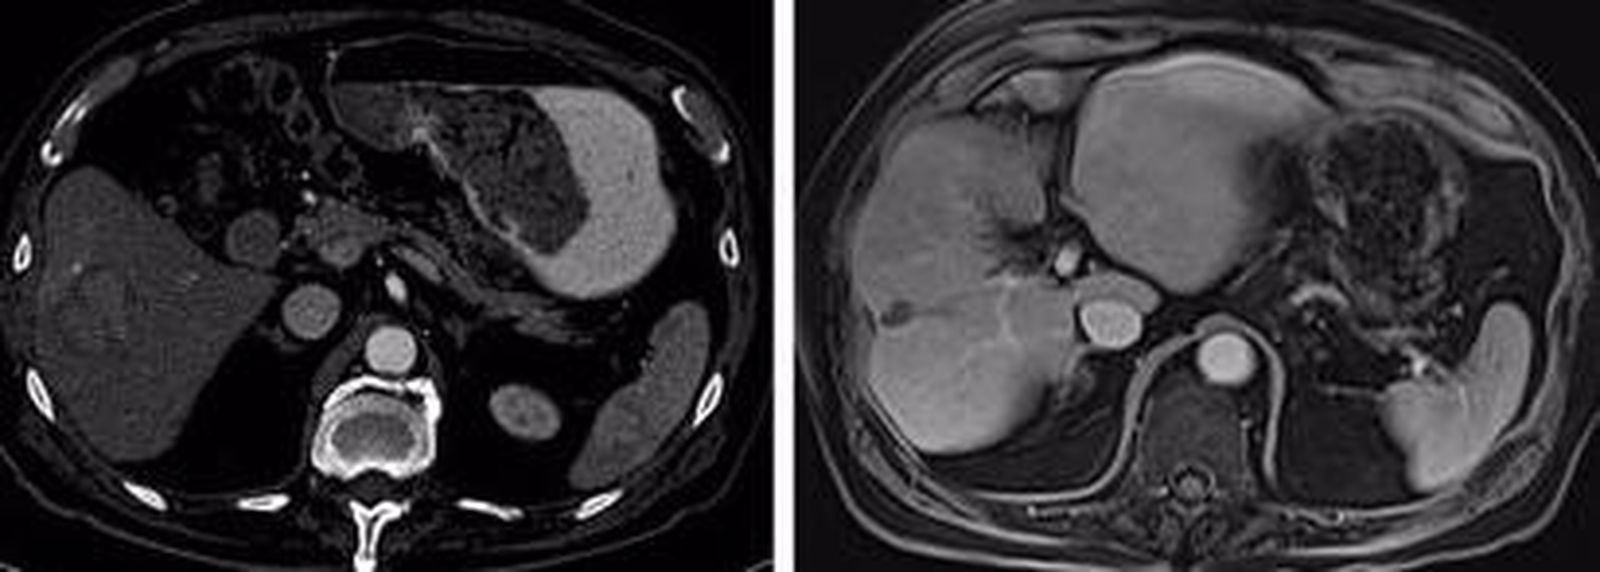

Ensayo en pacientes con cáncer de hígado